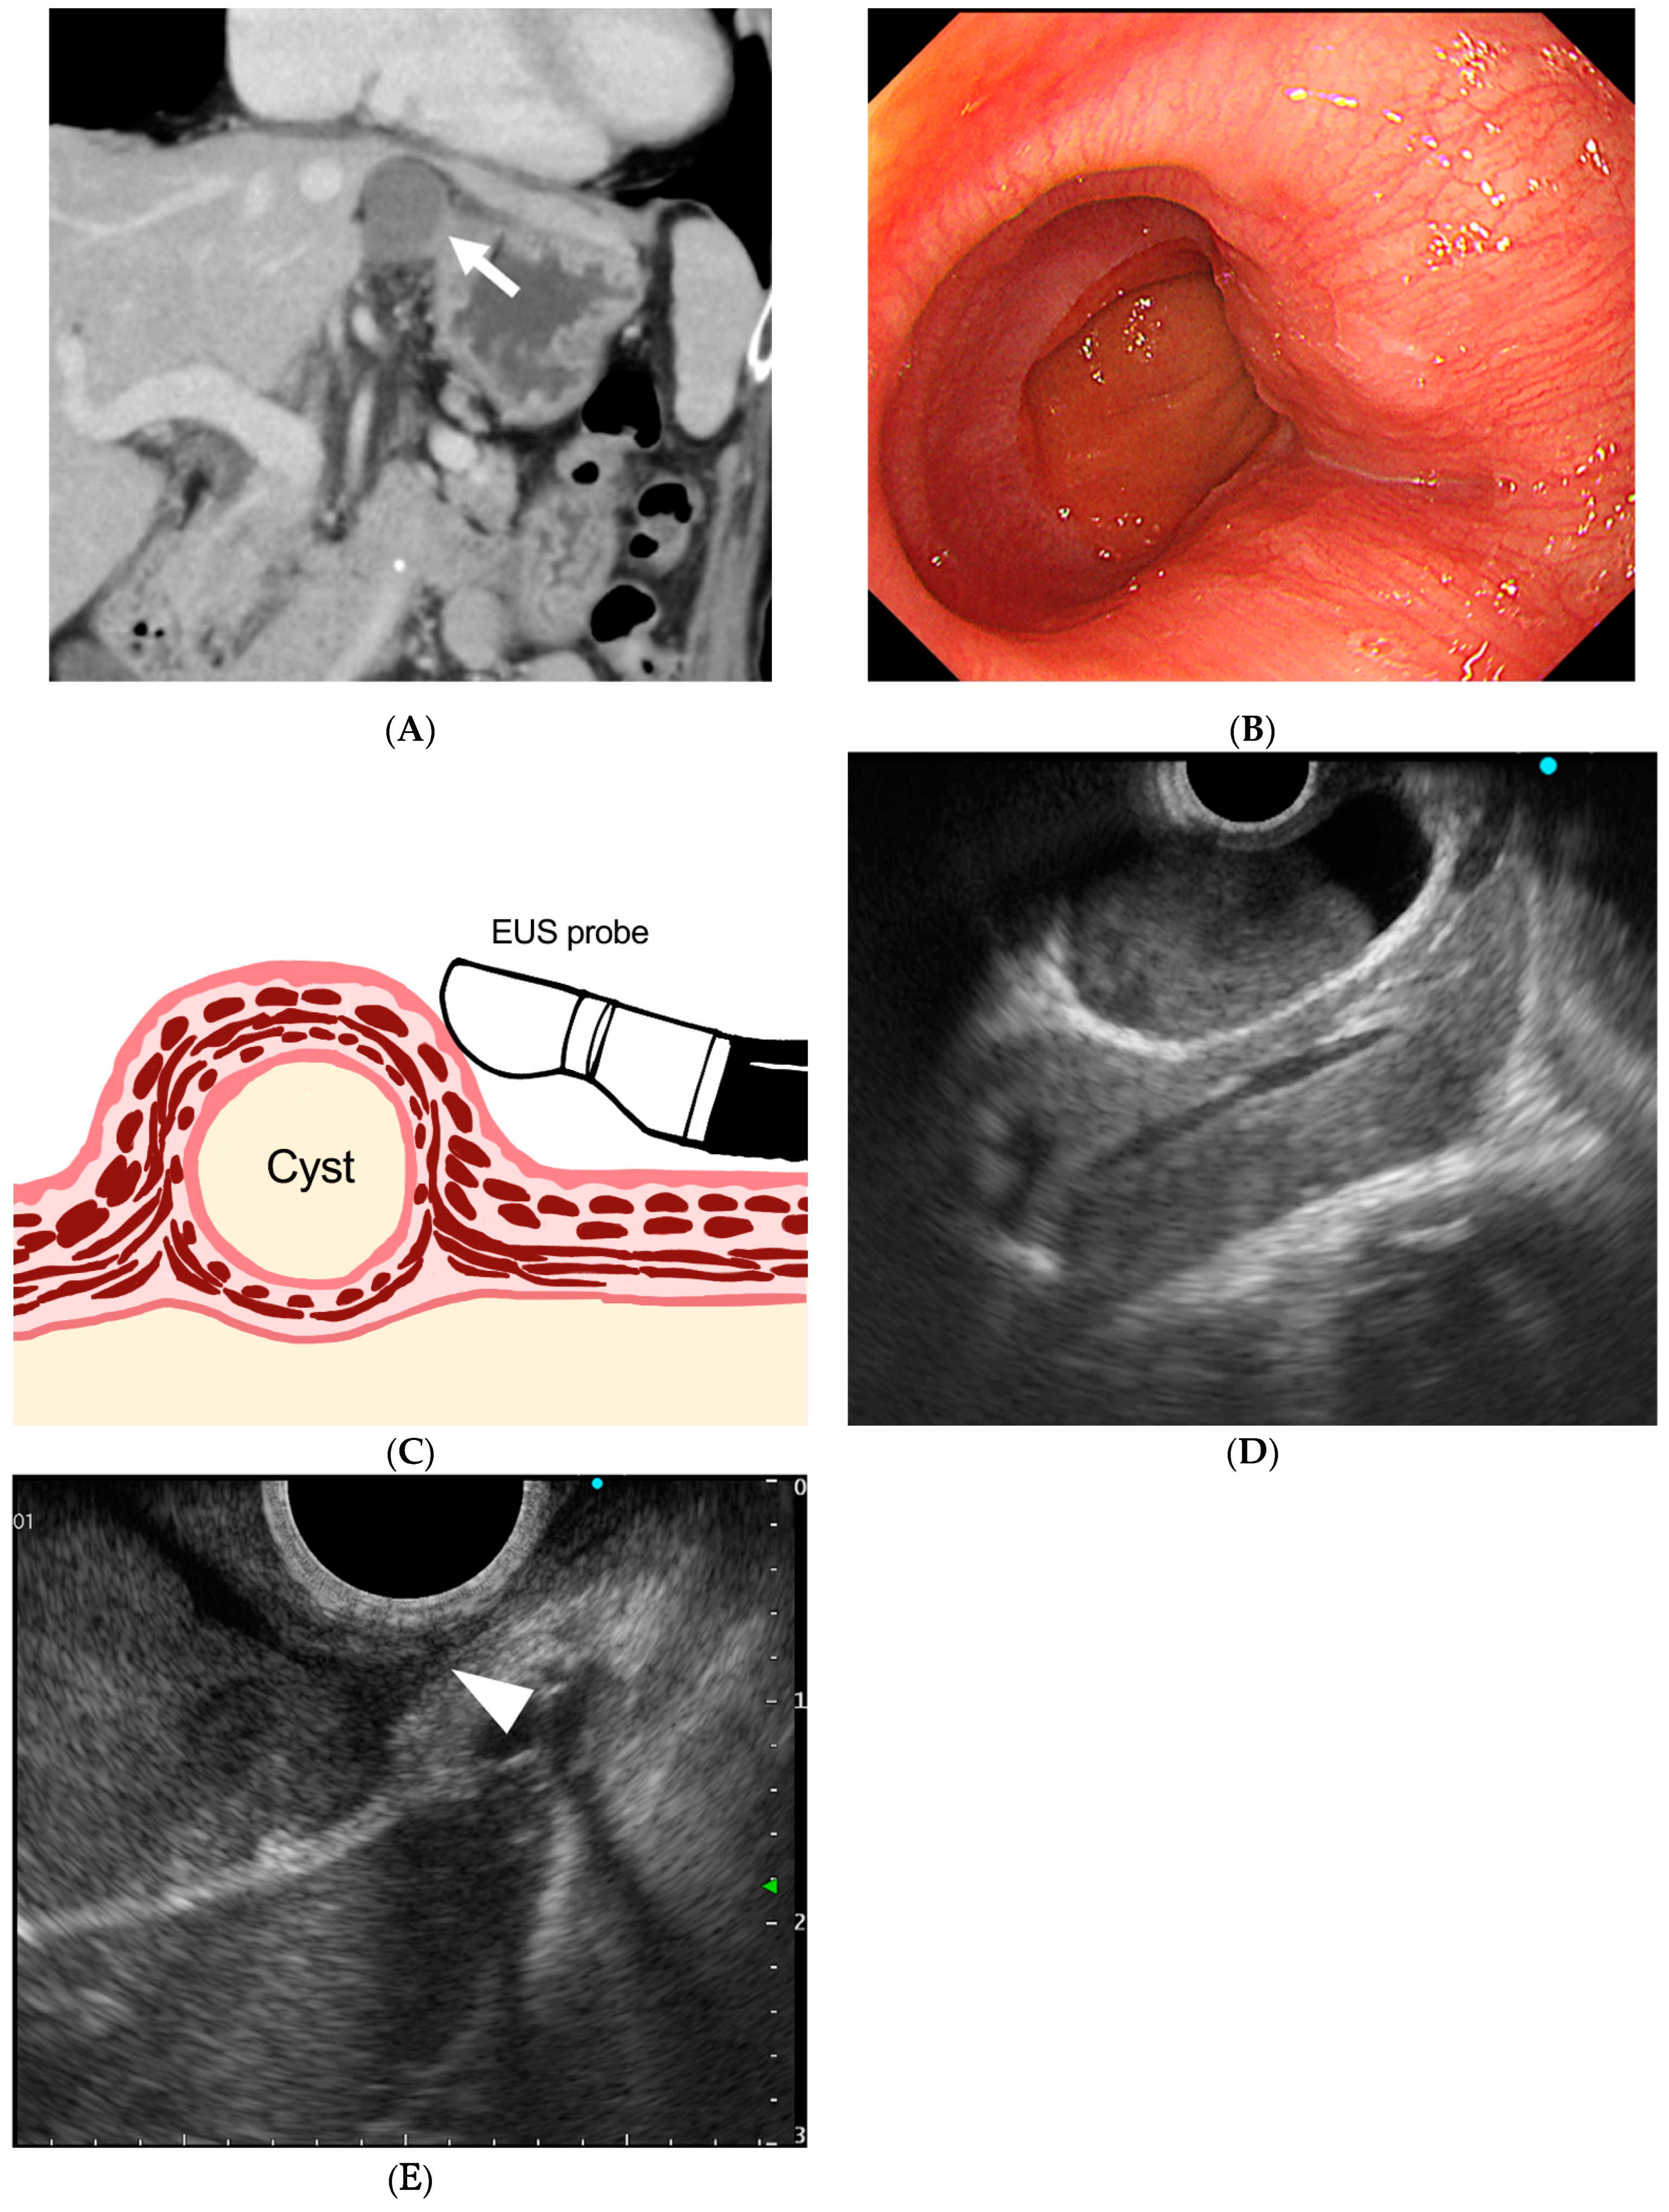

Preoperative Diagnosis of an Esophageal Duplication Cyst by Endoscopic Ultrasound Examination